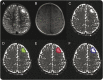

Methods: We retrospectively selected 23 consecutive patients (aged 0.4-19.6 years, mean age of 5.2; 13 female, 10 male) who underwent presurgical DTI and subsequent surgical resection between 2004 and 2013 from the University of California-Los Angeles TSC Clinic. We evaluated presurgical examinations including video-EEG, brain MRI, (18)F-fluorodeoxyglucose-PET, magnetic source imaging, and intraoperative electrocorticography for determining epileptogenic tubers. A total of 545 tubers, 33 epileptogenic and 512 nonepileptogenic, were identified. Two observers generated the regions of interest (ROIs) of tubers (ROI(tuber)), the 4-mm-thick ring-shaped ROIs surrounding the tubers (ROI(perituber)), and the combined ROIs (ROI(tuber+perituber)) in consensus and calculated maximum, minimum, mean, and median values of each DTI measure in each ROI for all tubers.

Results: The Mann-Whitney U test demonstrated that the epileptogenic group showed higher maximum ADC and radial diffusivity values in all ROIs, and that maximum ADC in ROI(tuber+perituber) showed the strongest difference (p = 0.001). Receiver operating characteristic analysis demonstrated that maximum ADC measurements in ROI(tuber+perituber) (area under curve = 0.68 ± 0.05, p < 0.001) had 81% sensitivity and 44% specificity for correctly identifying epileptogenic tubers with a cutoff value of 1.32 μm(2)/ms.